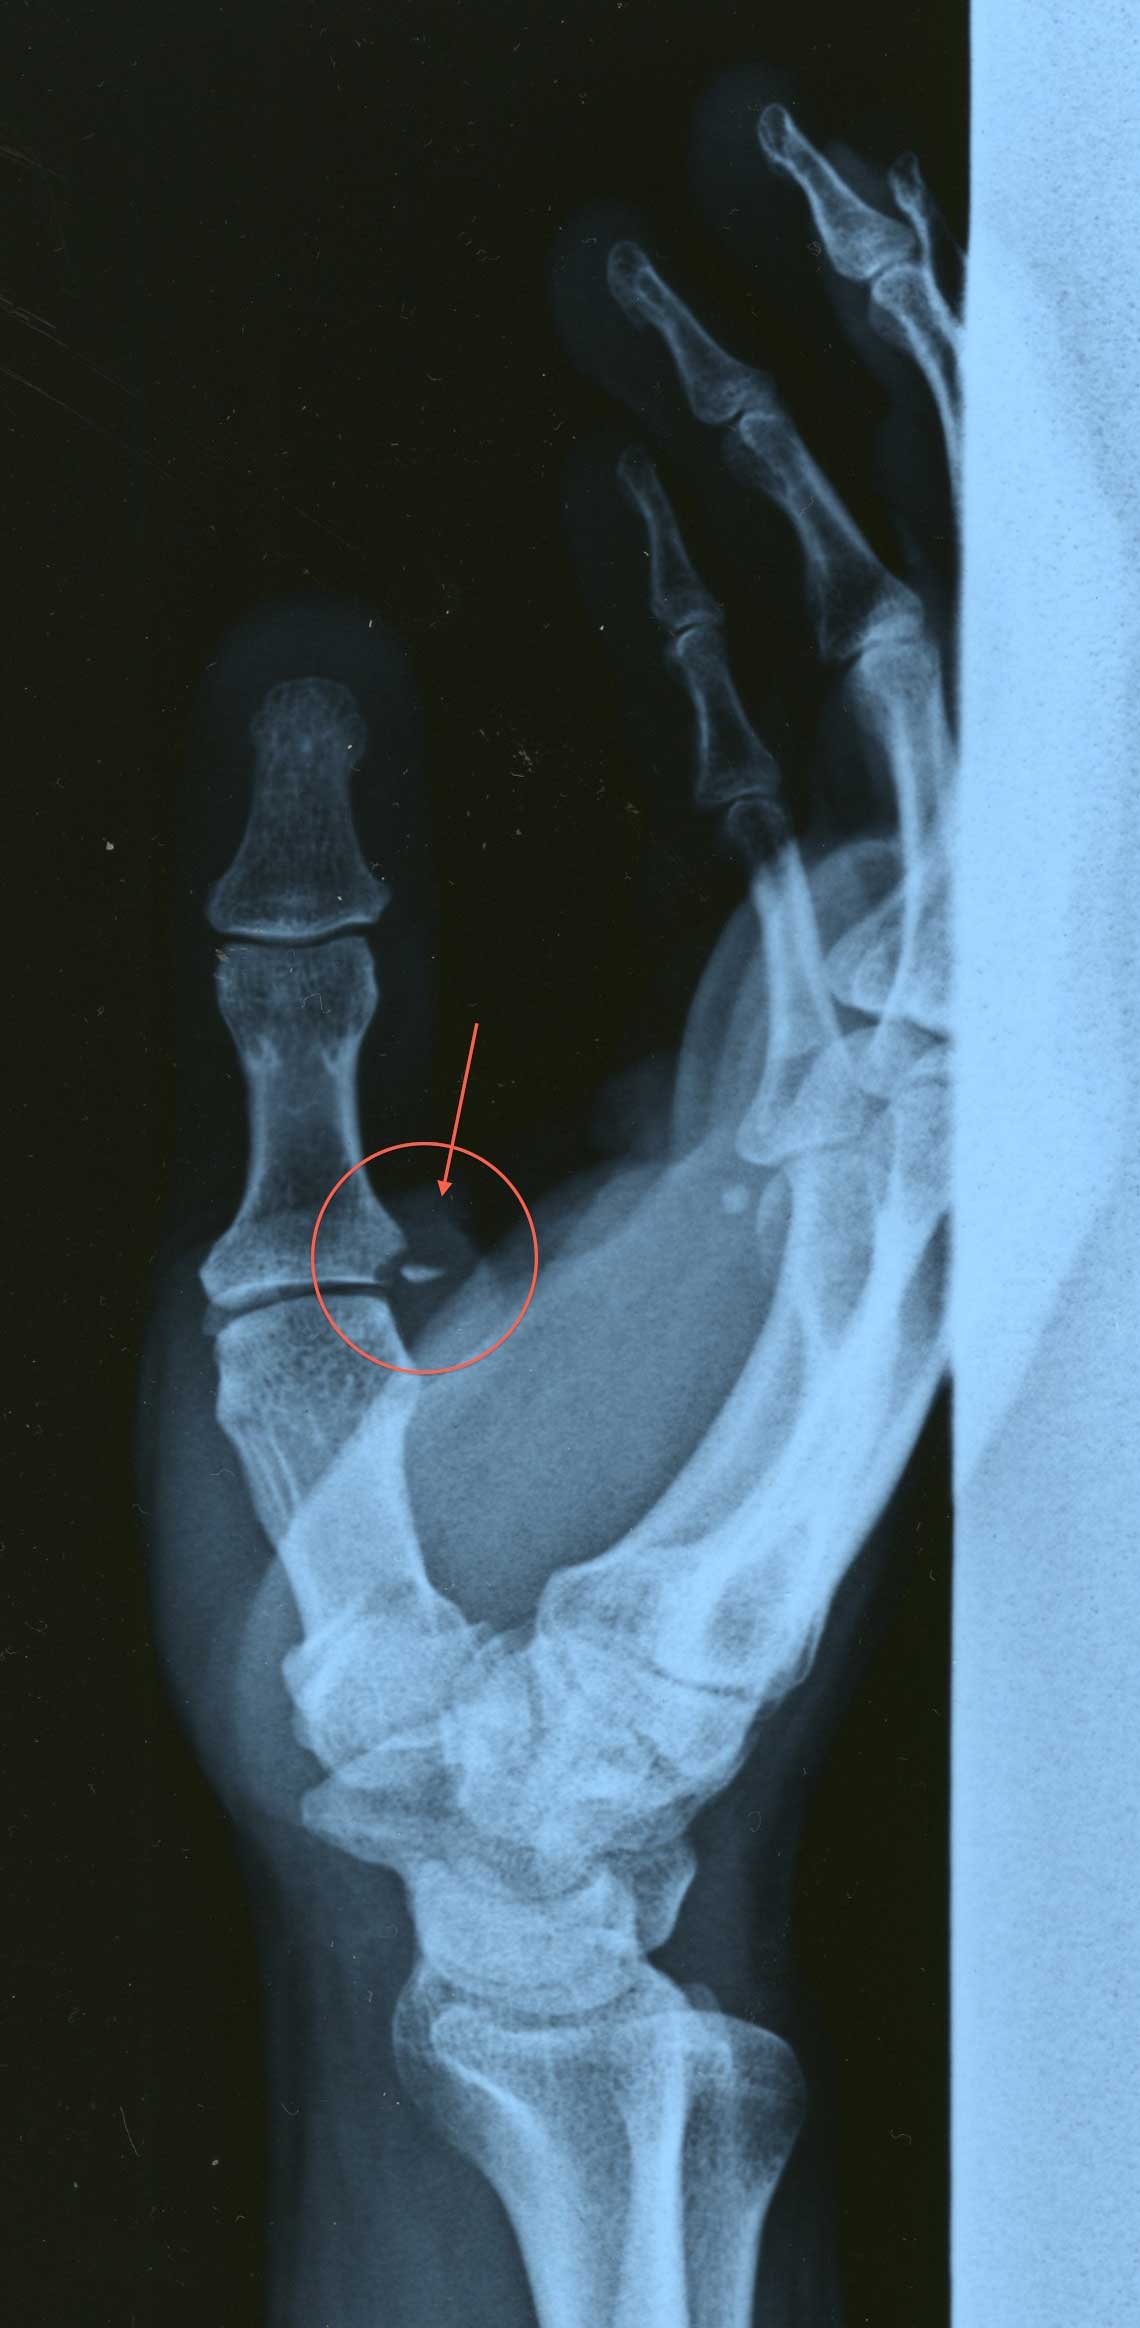

はい・・・右手の親指の根元を骨折してしまいました・・・

赤丸の所ですね・・・

階段から足を踏み外して落ちた時に、手のつき方が悪かったのですね・・・

お医者さんが言うには、手をついた時に、親指が外側に行き過ぎた為に折れたそうです。

そういう折れ方と言っておりました・・・